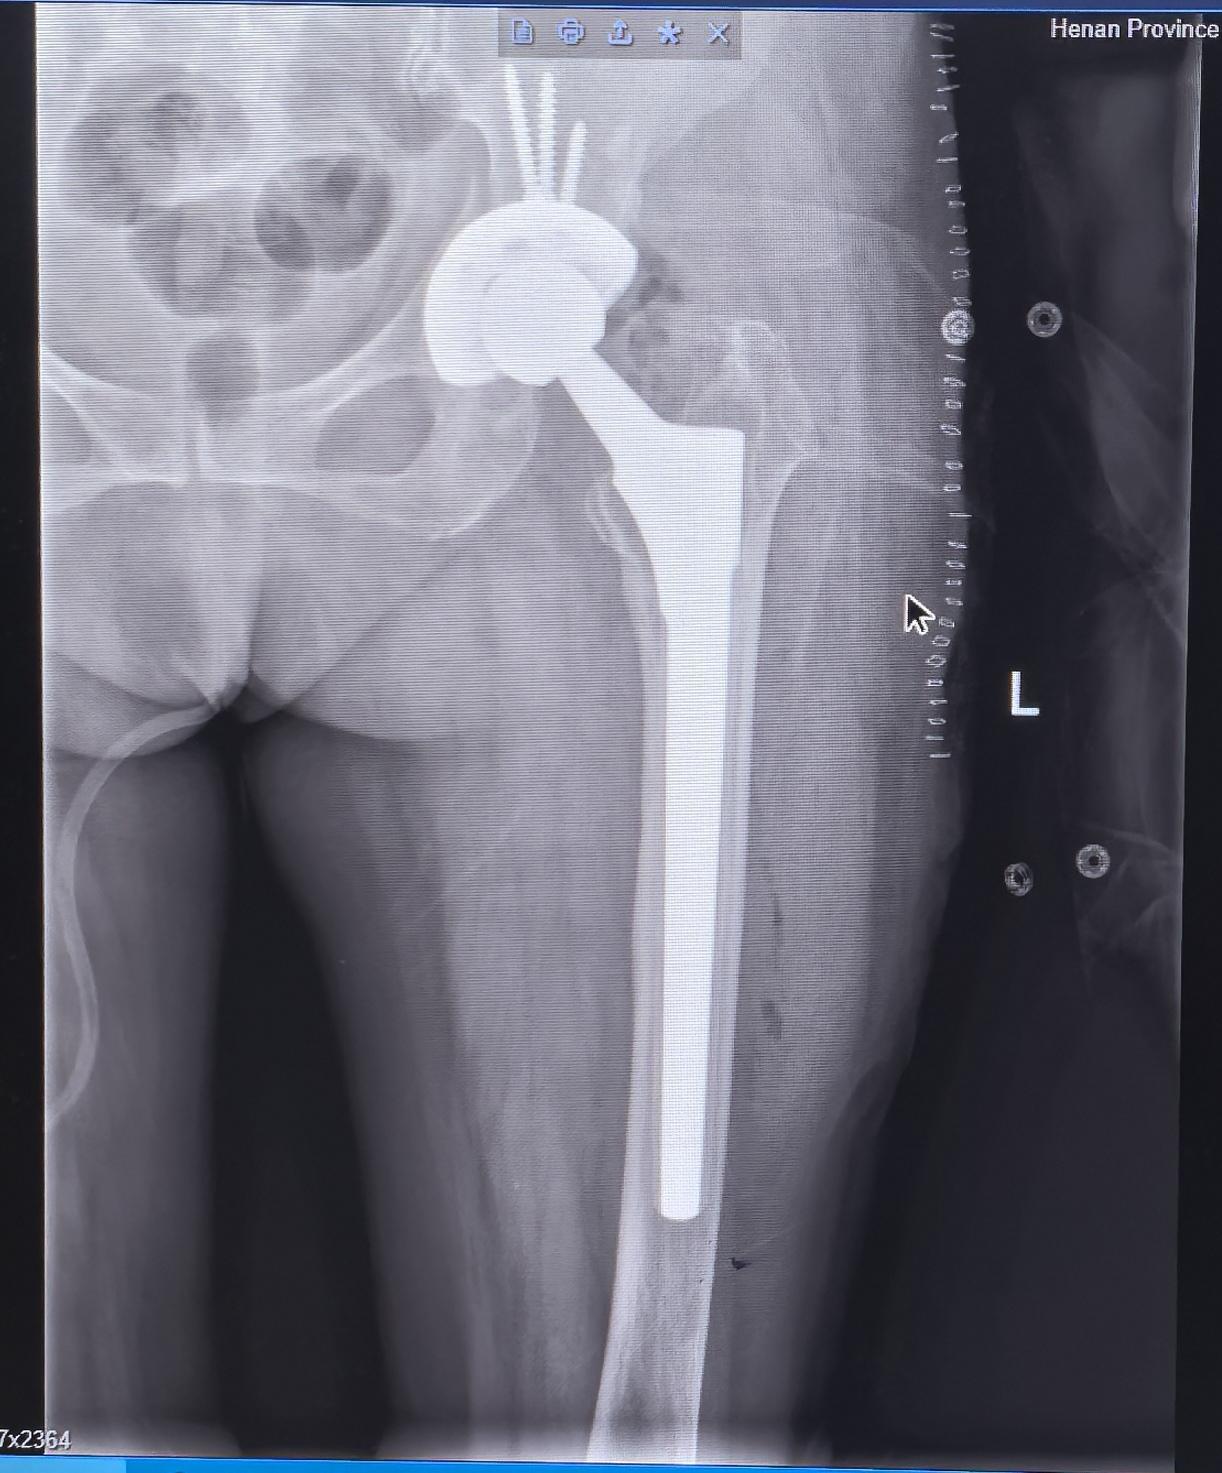

髋关节翻修,髋关节置换。股骨头坏死髋关节置换术后22年假体松动,83岁高龄二次翻修,手术顺利,再次“续命”20年🌹